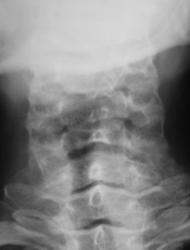

Пациент предъявляет жалобы на боли в плечевом суставе. Направлен на рентгенографию плечевого сустава хирургом. Со стороны плечевого сустава (рентгенограмма) патологических изменений не выявлено. Произведено исследование шейного отдела позвоночника.

Валентин Львович! Не могу посчитать позвонки, перекрываются углом нижней челюсти. Ну то, что имеется остеохондроз, это понятно. Аномалия развития в виде расщепления остистого отростка позвонка или C2 или C3 позвонка. Но откуда у С1 остистый отросток?

Что же касается данной шеи: считаю необходимым дообследования - рентгенография С1 позвонка "через рот", более информативно будет.